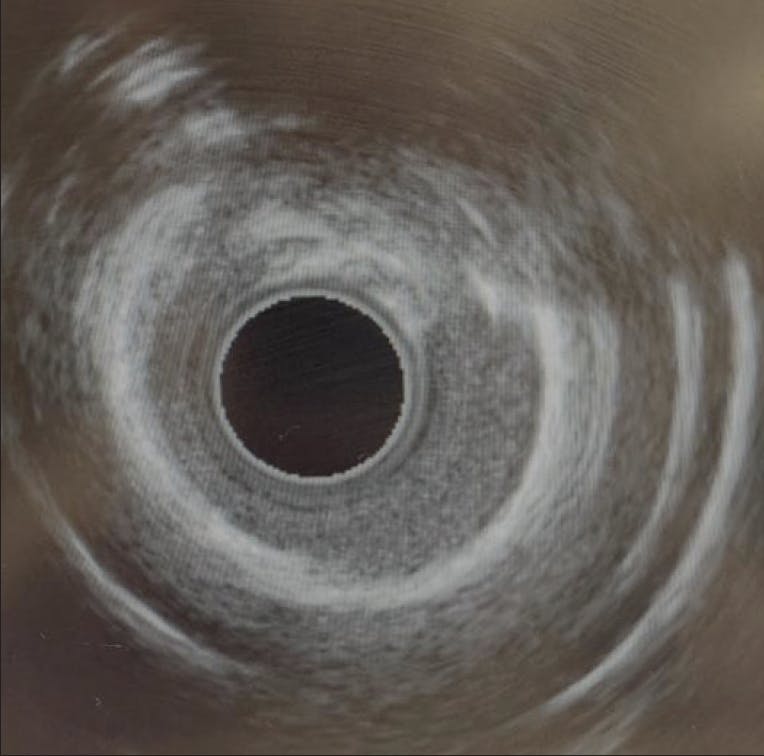

Unfortunately, the microcatheter would not cross the distal cap of the CTO, nor would a 1.5-mm semicompliant balloon, despite advancement of the guide extension. Given how close the microcatheter was able to get to the distal cap, we removed the Mongo wire and free-wired back into the R-PLV branch with a modified Rotofloppy wire (Boston Scientific Corporation) that had the radiopaque 0.014-inch segment cut short to facilitate wiring (Figure 3). We then performed rotational atherectomy of the CTO segment with a 1.5-mm burr over two 30-second runs, with the burr crossing the distal cap on the second run. The burr was removed and we used the microcatheter to switch the Rotofloppy wire out for the Runthrough wire. We then predilated the lesion with a 2.0-mm semicompliant balloon followed by a 2.5-mm NC balloon at nominal pressure with good expansion. Intravascular ultrasound (IVUS) was performed, showing some calcium fractures in the distal RCA but with residual concentric rings of thick calcium in the mid and proximal RCA (Figure 4).

Figure 4. Residual thick, concentric calcium after rotational atherectomy.

We then performed IVL of the vessel with a 4-mm Shockwave C2+ balloon (Shockwave Medical), delivering all 120 pulses throughout the vessel. After that, we predilated the entire vessel with a 4-mm NC balloon with excellent expansion. Using the guide extension, we placed a 4- X 48-mm drug-eluting stent (DES) in the distal vessel, overlapped with a 4- X 38-mm DES in the mid vessel, and again overlapped with a 4- X 20-mm DES in the proximal RCA to the ostium. All stents were postdilated with a 4.5-mm NC balloon to high pressure.